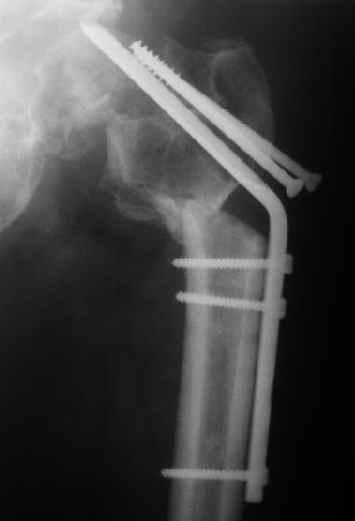

Мужчину 56 лет оперировали у нас в августе 2003 г. - вальгизируюшая остеотомия из-за позднего (через 2 мес. после травмы) поступления с переломом шейки бедра (картинки 1,2). Курильщик, соматической патологии не было. Сейчас поступил с жалобами на проблемы в области тазобедренного сустава, на снимках 3,4 видно вырезывание клинка.Чтоб можно посоветовать в этой ситуации? Заранее спасибо.

A male 56 years old was operated in Aug 2003 - valgus osteotomy performed because of delayed admission with neck fracture (2 months) images 1,2. Smoker, no other major medical problem. Now he re-admitted with the images 3,4.What would you do in the situation?THX in advance.

The osteotomy seems to be showing bony union. (New bone at the medial aspect). There is a big step in the union. The distal fragment is way out laterally.There is overiding of the neck over the head. The screws are out superiorly and the blade also coming out. There is no union of the neck fracture. The head does not seem to be normal- distorted in shape and probably starting of AVN too.

If replacement is considered, the osteotomy has to be realigned as mentioned earlier.

Possible reasons why this happened: 1) There is not sufficient purchase of the screws into the head. In fact one can see some threads crossing the fracture site. This will prevent union across. Even the blade probably has less purchase. 2) After the osteotomy the distal fragment will have to be pushed more medially ( as we used to do McMurray's osteotomy 30 years ago) or abducted and fixed so the the fracture line becomes horizontal when the limb is brought to neutral.There is no abduction (so it is not a valgus osteotomy) and in fact the fragment is pulled out laterally. The fracture line has remained vertical and on weight bearing the shearing forces have pulled the implants superiorly. I am waiting for the answer from the replacement specialists.